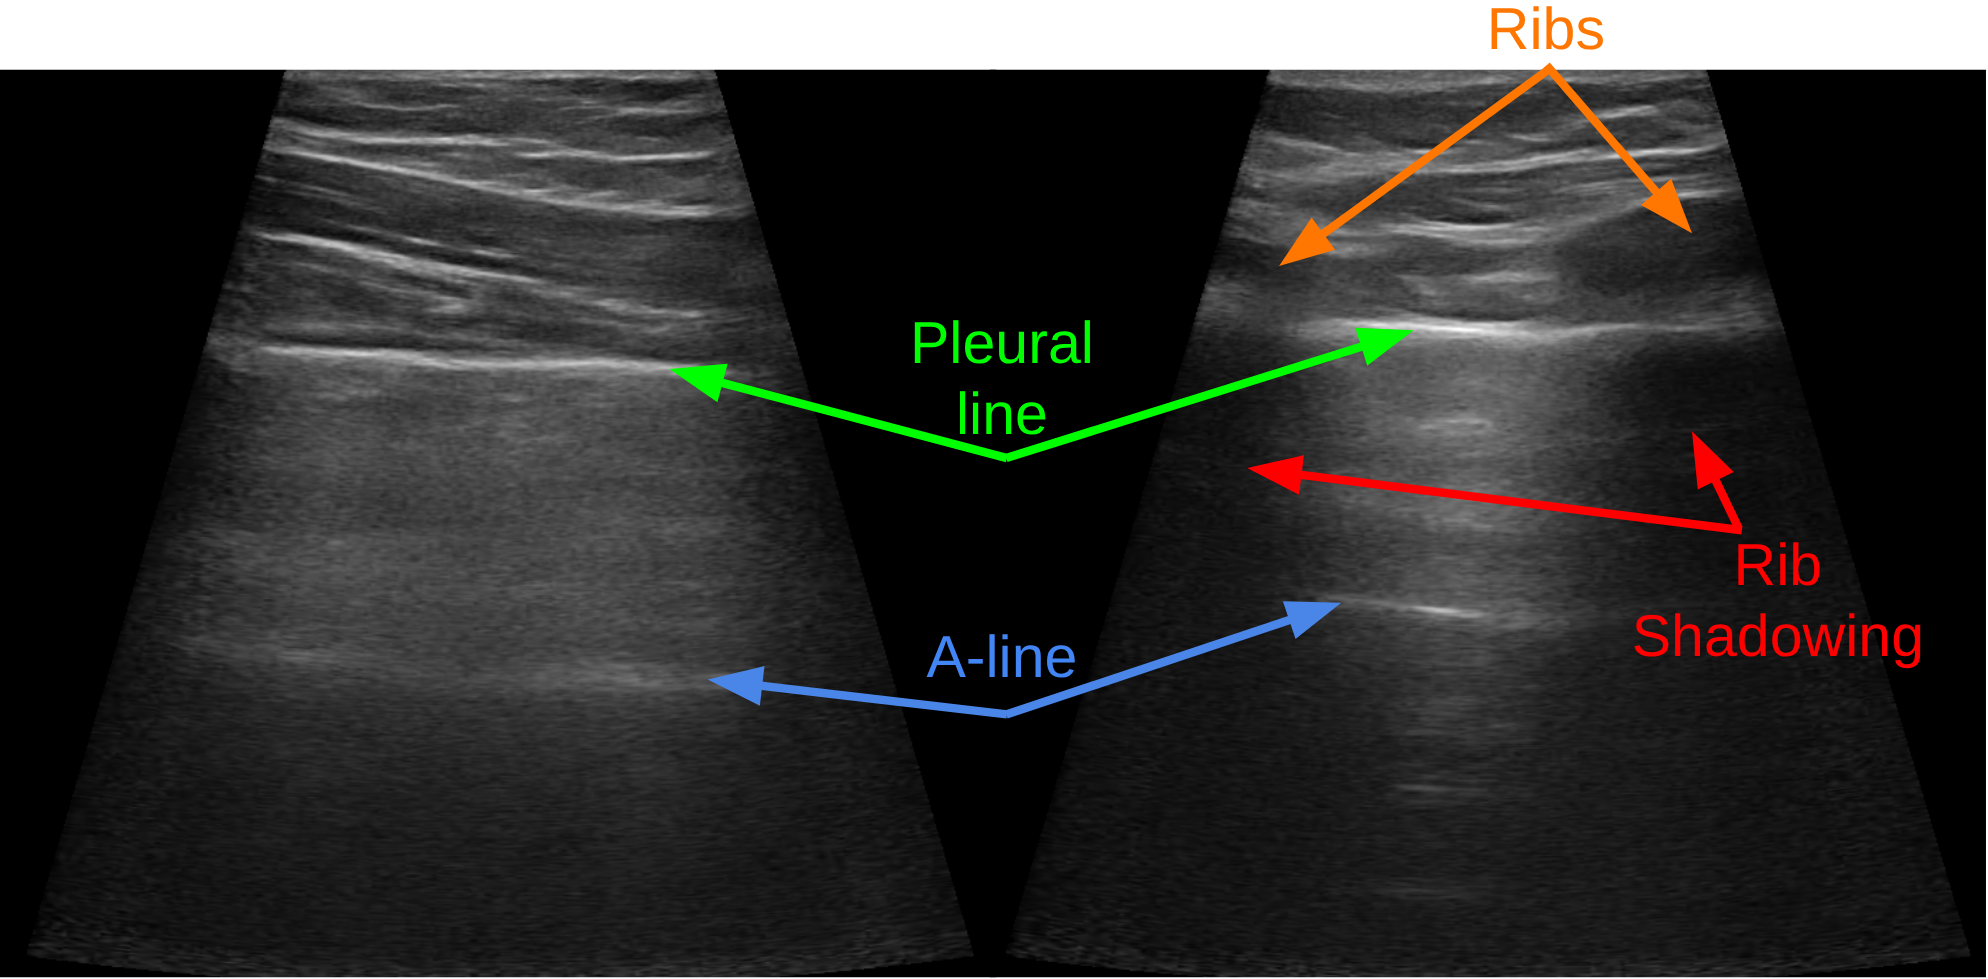

In LUS, the probe should be placed in the intercostal areas [21] to avoid the shadowing effect due to the presence of the ribs [14]. Detecting the bones and thus placing the probe, mounted on the end-effector of the manipulator, in such a narrow area could become a complex task. In the case of teleoperated robotic ultrasound exams, in particular, standard visual and haptic feedback, fundamental in in-person exams, might not suffice. For example, when the robot is in close proximity to the patient, the patient’s view captured by a fixed RGB camera might be occluded by the robot. If the camera is mounted on the robot end-effector instead, it might be too close to the patient, reducing the field of view. In such a case, a 3D model, which includes the anatomical features of the patient, such as the rib cage in the case of LUS, and the target pose of the robot, might provide great support. Also, when the probe is in contact with the body, with standard haptic feedback, it is not easy to distinguish if the probe is located on top of a bone or soft tissue, and thus the practitioner should rely only on the ultrasound image. Another relevant issue is represented by the low repeatability and the high subjectivity of the operations, as the success of the exam depends very much on the practitioner’s ability to cope with the anatomical variability of patients.

Ultrasound image quality highly depends on the probe orientation, since specular reflection of the ultrasound beam is maximised when the probe is positioned orthogonally. Specifically in LUS, optimal acquisition requires maintaining the probe in the transverse orientation, which means parallel to the ribs and perpendicular to the pleural line, to avoid the rib shadowing. Achieving and maintaining such an orientation during teleoperation can be particularly challenging. To address this, we leveraged the volumetric body model to derive the ideal orientation of the ultrasound probe. We defined the coordinate frame of the probe such that the -axis points outward from the sensor, while the -axis extends in the image lateral direction. The volumetric model provides valuable information about the curvature of the surface being approached. Accordingly, during each control cycle, we compute the average normal vector of the neighborhood of (for practical use, approx. 30 triangles represent a good neighbourhood). The obtained vector is used to define the -axis of . The -axis of is determined by projecting the ribs’ extension axis onto the plane orthogonal to the -axis, and the -axis is then orthogonal to the previous axes. Note that, since the model might not be sufficiently accurate and the lung surface is not always parallel to the skin, is in general suboptimal. For this reason, we leave the task of finding the optimal orientation to the physician by looking at the LUS data, in a shared control fashion. One possibility to enforce a constraint on the orientation is defining conical regions centred on that restrict the allowable motion of the rotation matrix axis. We would like to enforce

The goal of this experiment was to evaluate if, with naïve subjects, there are significant improvements (both objective and perceived) of the proposed method with respect to the baseline. For this reason, after each attempt, the subject was required to fill in a NASA TLX questionnaire. In light of the challenges associated with the objective assessment of LUS acquisitions due to the lack of image-based metrics to evaluate the quality of LUS images, we compared the methodologies based on the duration of the examinations and the number of valid acquisitions. Thus, the duration was measured from the beginning of the 2 minutes time budget until a LUS valid acquisition. The acquisition was deemed valid if the pleural line was horizontal on the image and visible for approx. of its horizontal extension (see Figure 5) and maintained for at least 2 s in the image and was measured after the end of the experiment, which was always performed for 8 minutes. After the end of the examination, we evaluated the recorded US videos and marked the valid acquisitions. In case the acquisition was not valid within the 2 minutes time budget, we considered it a failure, and we added 2 minutes to the total time of the examination.